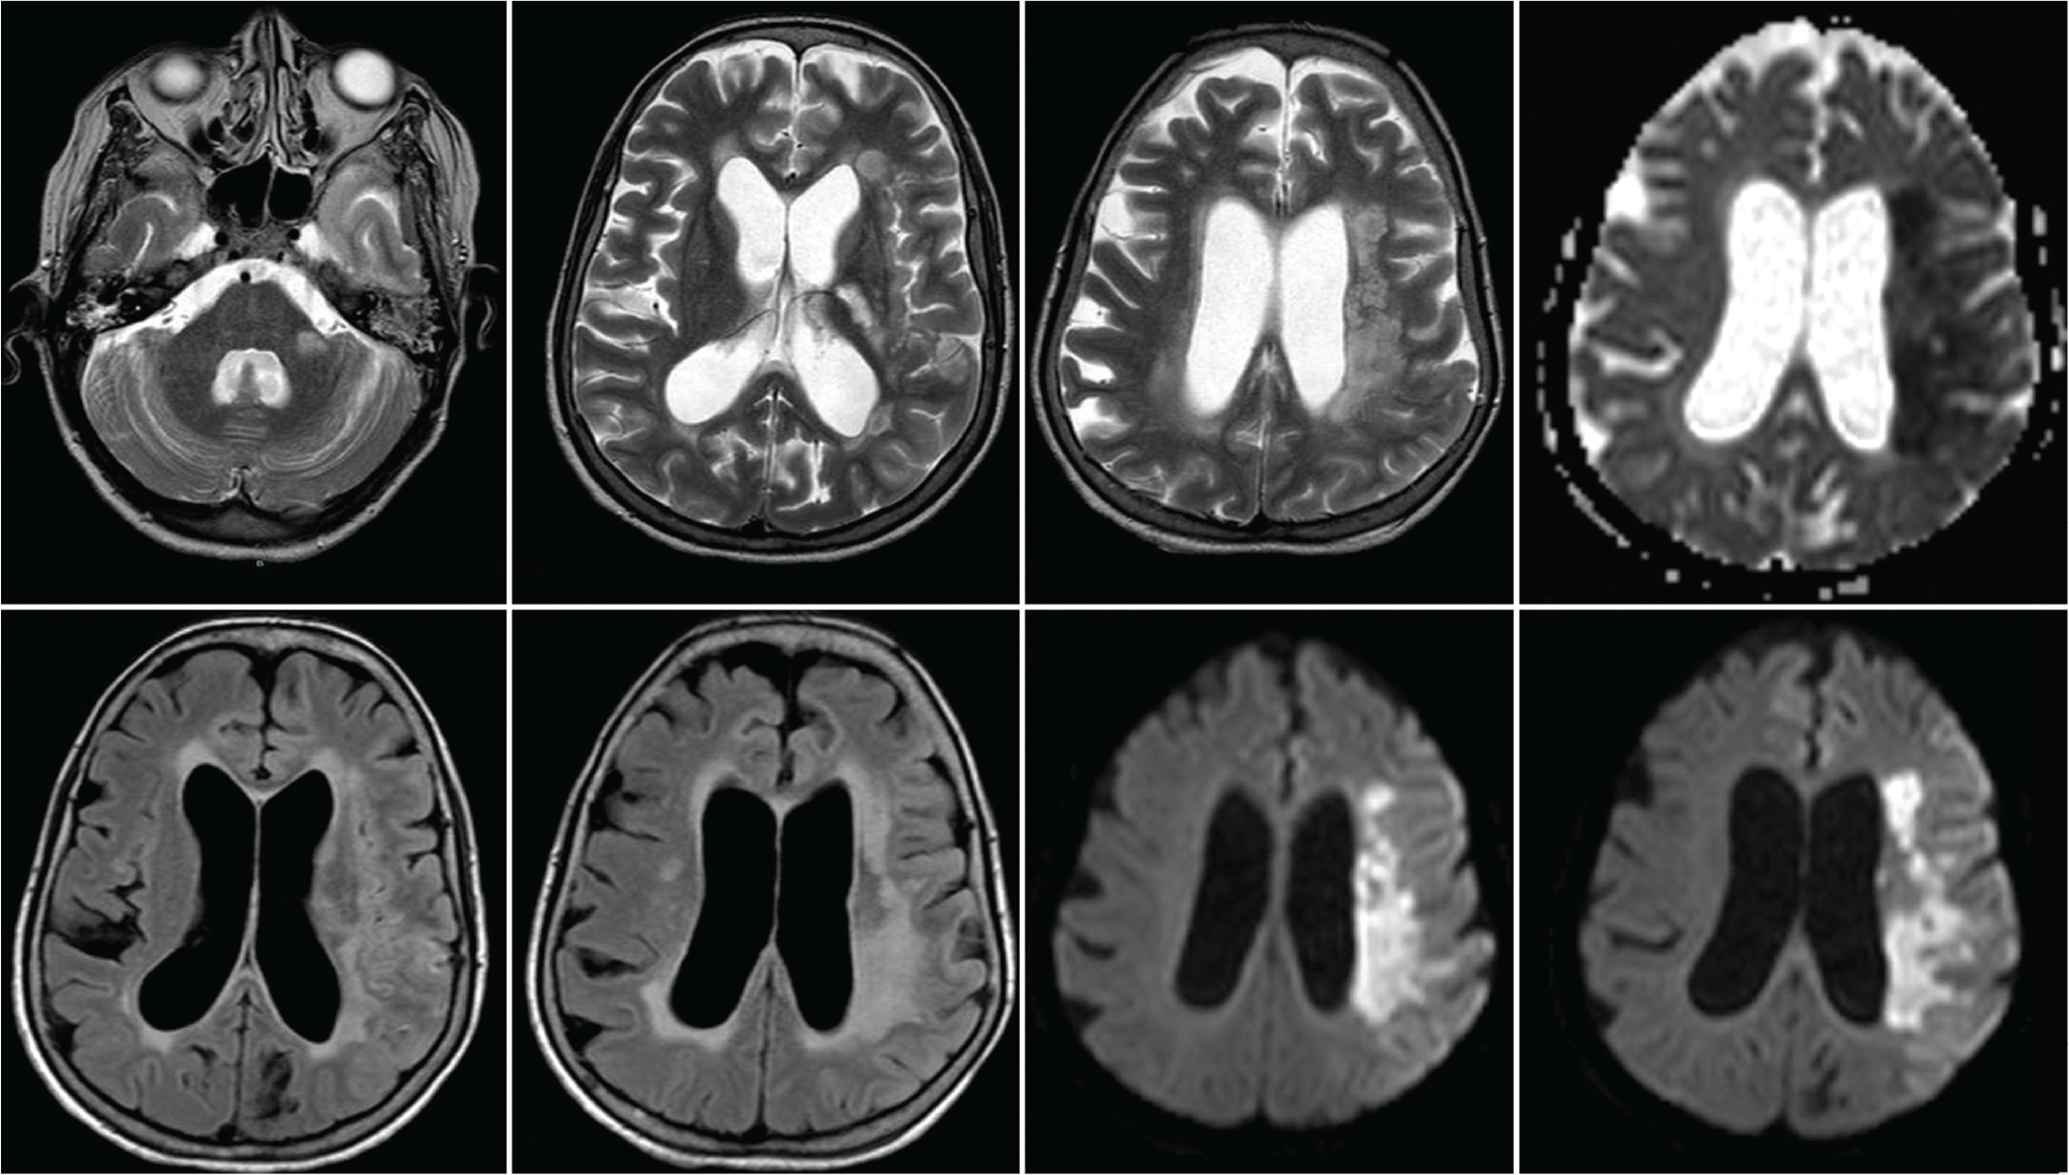

A 60-year-old female presented to the emergency department with headache, neck pain, and low back pain that started 6 months ago. Two weeks prior to presentation, she had difficulty walking with no sphincter control disturbance or sensory symptoms. She had no history of diabetes mellitus, infectious disease, or dyslipidemia. She is a housewife who is married and living with her children. Although no family history of tuberculosis was documented, she gave a strong history of contact with a patient who has open pulmonary tuberculosis that was not on treatment. Her systemic examination was normal including vital signs, lung auscultation, cardiac examination, and skin inspection. As part of her investigations, she had normal complete blood count, renal and liver function tests, and electrolytes including sodium, magnesium, and phosphate. Her erythrocyte sedimentation rate was high at 64. The result of her human immunodeficiency virus test was negative, and the chest X-ray was normal. Magnetic Resonance Imaging (MRI) of the whole spine revealed intramedullary dorsal (thoracic) ring-enhancing lesion at the level of T10–T11 (Figure 1). MRI of the brain showed diffuse meningeal enhancement with no intraparenchymal cerebral or cerebellar lesions (Figure 2). Cerebrospinal Fluid (CSF) analysis revealed a lymphocytic pleocytosis with a leukocyte count of 90 cells (reference range, 0–5), lymphocyte predominance (87%), raised protein of 236 mg/dL (reference range, 15–60 mg/100 mL), low CSF glucose 18 mg/dL (reference range, 50–80 mg/100 mL). CSF Gram stain, culture, and sensitivity were negative for all bacteria including mycobacterium tuberculosis. In addition, the Polymerase Chain Reaction (PCR) for viral, bacterial, and mycobacterial DNA was negative. Unfortunately, and despite tuberculous meningitis being the most likely diagnosis based on clinical and paraclinical data, the patient was not started on antituberculous medications. The treating infectious diseases consultant requested a brain and meningeal biopsy, which was declined by the patient’s family. The consultant refused to start the patient on antituberculous medications if no tissue is obtained for pathological confirmation of diagnosis. The patient’s condition deteriorated, and she was admitted to the intensive care unit with intubation and mechanical ventilation. The patient developed status epilepticus and was started on levetiracetam 1000 mg twice daily. She developed focal neurological deficits and multiple cranial nerve involvement. A repeated MRI of the brain showed an acute ischemic infarction with restricted left capsular, medial temporal, and hippocampal lesions in the apparent diffusion coefficient map (Figure 3). It also revealed persistence and even worsening of meningeal enhancement. Repeated CSF analysis revealed low glucose at 8, high protein at 255, and white blood cells count of 190 with lymphocytes (85%) and neutrophils (15%). Owing to the family request (based on neurology team recommendation) as well as clinical and radiological deterioration, the patient was started on antituberculous medications (rifampicin 600 mg, isoniazid 300 mg, pyrazinamide 1500 mg, and ethambutol 1200 mg) and oral corticosteroids through a nasogastric tube. This was several weeks after admission to the intensive care unit. Despite the advanced stage of the disease, the development of endarteritis obliterans with multiple ischemic strokes, and poor clinical condition, the patient’s condition improved, and her seizures stopped. Her neurological status improved, and she became more alert with better power in all limbs, and after 3 weeks, she was weaned off ventilation and was extubated. The patient was transferred to a rehabilitation center for an aggressive physiotherapy regimen, and the family was instructed to continue the antituberculous medications for a full 12-month period. Unfortunately, the patient died from neurological complications related to tuberculous meningitis (multiple infarcts with superadded massive pulmonary embolism).

Magnetic Resonance Imaging (MRI) scan of the brain showing an acute ischemic infarction with restricted left capsular, medial temporal, and hippocampal lesions in the apparent diffusion coefficient map.